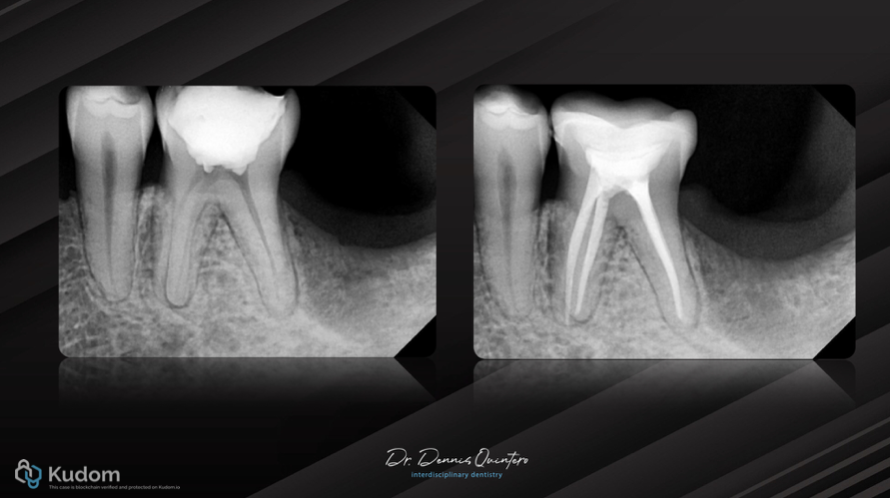

Fig. 1

. Tooth 3.6

. Initial X-ray with deep provisional material close to the pulp.

X-ray final result from endo to final conservative restoration